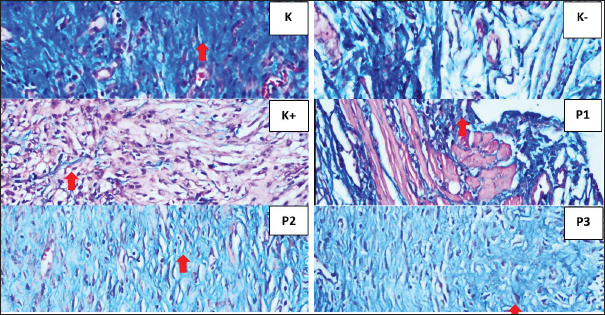

The lowest IL-10 levels were observed in the 50% P. crocatum extract gel group=247,515. The lowest TGF-B1 expression observed in the 25% P. crocatum extract gel group=4,033. The highest VEGF expression was observed in the 25% P. crocatum extract gel group=11.45. The highest collagen density was found in the 50% Piper crocatum extract gel group=0.833, and the smallest percentage of wound area approaching normal wounds was in the 50% P. crocatum extract gel group, which was 11,338 (Fig. 1). TGF-β1 expression is shown as brown color in rat skin (Rattus norvegicus), seen in the 50% P. crocatum extract gel group (P3), with the lowest value=4 (Fig. 2). Based on IHC examination using Santa Cruz antibodies, the VEGF expression was observed in large blood vessels with brown endothelium visible in the skin of rats in the 25% P. crocatum extract gel group (P2), with the highest number 13 (Fig. 3). The group with the highest collagen density was the 50% P. crocatum extract gel (P3)=0.833 (Fig. 4). The group with wound healing approaching normal wounds was the 50% P. crocatum extract gel group (P3) even though almost all of them were diagnosed with malignant tumors (Figs. 5 and 6). Path analysis of the direct and indirect effects of P. crocatum extract (Fig. 7) and mechanism of effect of P. crocatum extract on IL-10 levels, TGF-β1 expression, VEGF expression, and collagen density in post-excision wounds of mammary tumors of female Wistar rats (Fig. 8).

Fig. 4. Histopathological features of Wistar rat skin post-excision of mammary tumors after treatment for 14 days in each group, as indicated by collagen (⇧) K (scoring 3) K- (scoring 0), K+ (scoring 1), P1 (scoring 2), P2 (scoring 1), and P3 (scoring 3) (HE staining, magnification of 400×).